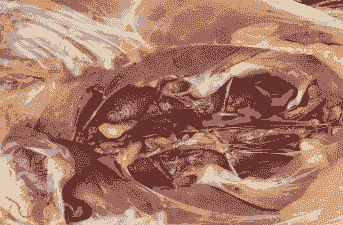

抗生素:无菌操作用针管抽取腹腔积液,然后注入0.05%的青霉素普鲁卡因0.2-0.3 mL,1%速尿注射液0.3 mL,严重病例同时肌注10%安钠加0.1 mL。全群饮水中加入0.05%维生素C,或在饲料中添加氯化钙、利尿剂、健脾利水的中草药等。